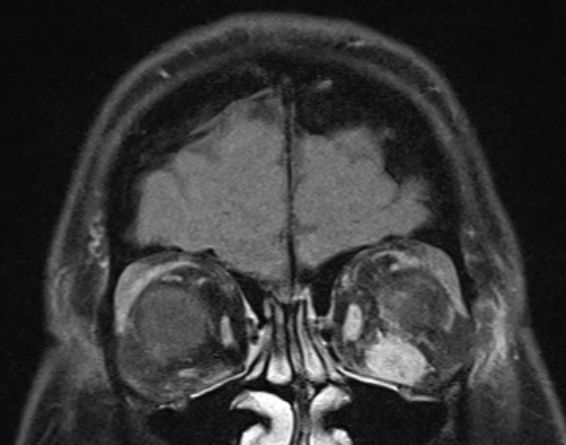

MRT eines retroorbitalen Lymphoms |